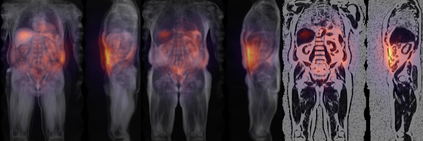

Along with rich health-related metadata, an ongoing imaging study has acquired MRI of over 40,000 male and female UK Biobank participants aged 44-82 since 2014. Phenotypes derived from these images, such as measurements of body composition, can reveal new links between genetics, cardiovascular disease, and metabolic conditions. In this retrospective study, six measurements of body composition were automatically estimated by ResNet50 neural networks for image-based regression from neck-to-knee body MRI. Despite the potential for high speed and accuracy, these networks produce no output segmentations that could indicate the reliability of individual measurements. The presented experiments therefore examine mean-variance regression and ensembling for predictive uncertainty estimation, which can quantify individual measurement errors and thereby help to identify potential outliers, anomalies, and other failure cases automatically. In 10-fold cross-validation on data of about 8,500 subjects, mean-variance regression and ensembling showed complementary benefits, reducing the mean absolute error across all predictions by 12%. Both improved the calibration of uncertainties and their ability to identify high prediction errors. With intra-class correlation coefficients (ICC) above 0.97, all targets except the liver fat content yielded relative measurement errors below 5%. Testing on another 1,000 subjects showed consistent performance, and the method was finally deployed for inference to 30,000 subjects with missing reference values. The results indicate that deep regression ensembles could ultimately provide automated, uncertainty-aware measurements of body composition for more than 120,000 UK Biobank neck-to-knee body MRI that are to be acquired within the coming years.